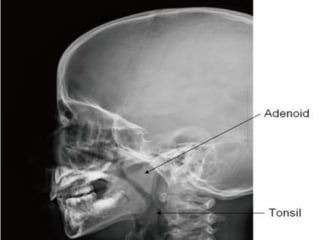

 Roof and Posterior wall:

• Continuous slope, opposite the posterior part of body of

sphenoid, basiocciput and anterior arch of atlas.

• Adenoids- In the roof and the posterior wall of lymphoid

tissue.

 Lateral wall: •Pharyngeal opening of the eustachian tube. • Tubal elevation bounds the tubal opening. • Salpingopharyngeal fold. • Leveator palatani. • Fossa of Rosenmuller.  Roof and Posterior wall: • Continuous slope, opposite the posterior part of body of sphenoid, basiocciput and anterior arch of atlas. • Adenoids- In the roof and the posterior wall of lymphoid tissue.